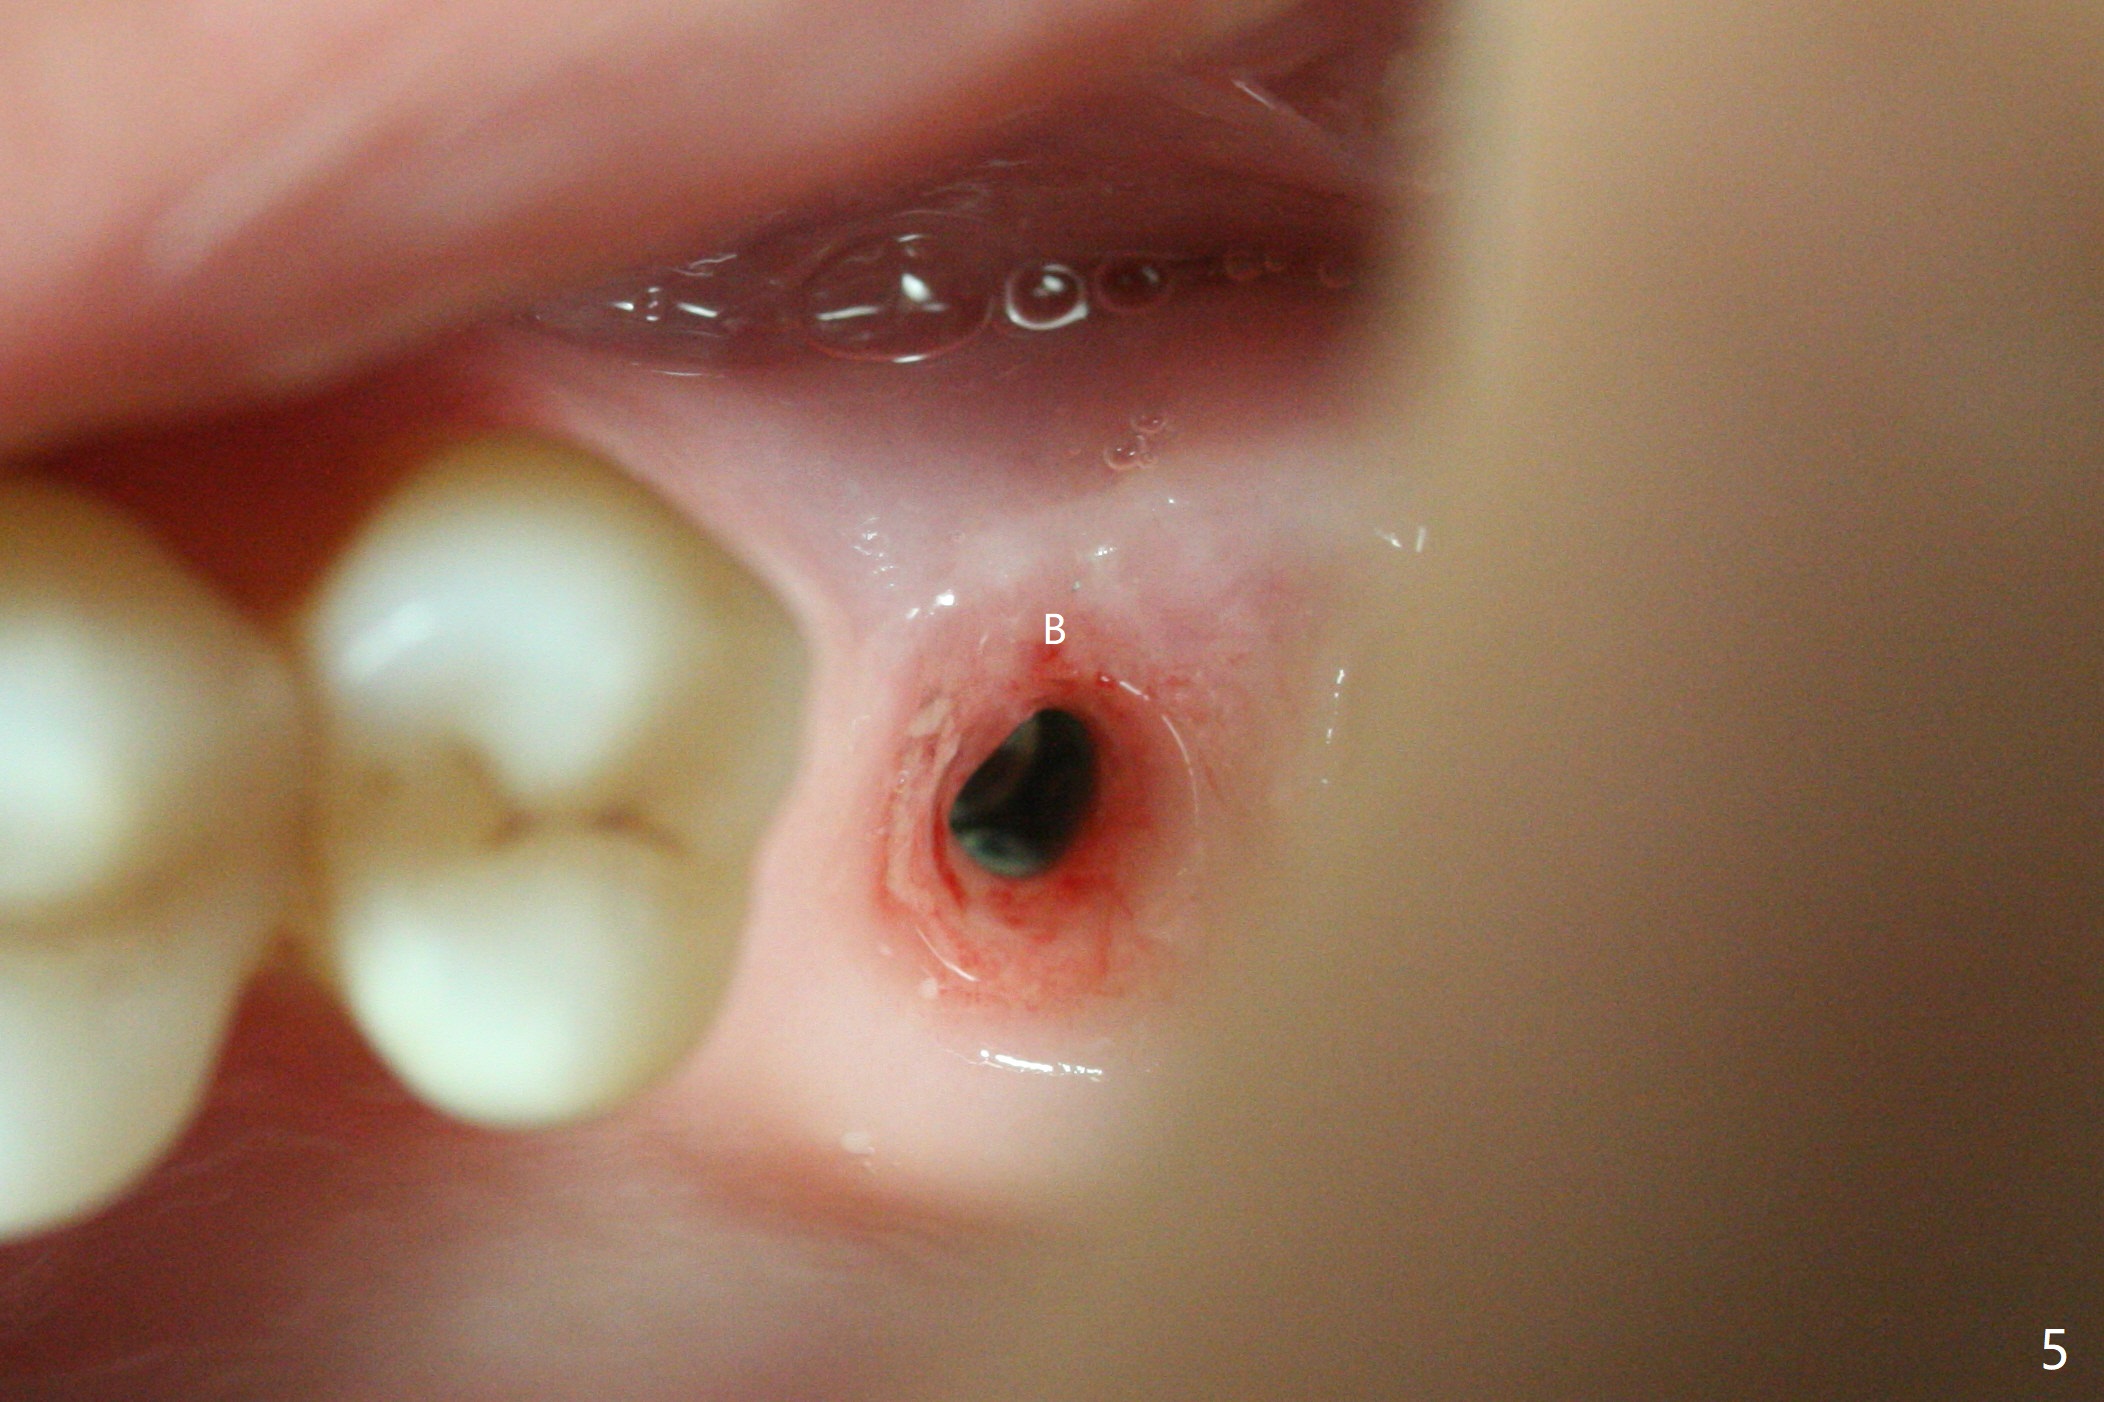

A 57-year-old woman complains of bad smell while use of water flosser between 11 and 21 months post cementation of implant crown at #14 (Fig.1,2). Bone loss is more obvious with CBCT (Fig.3,4), in spite of apparently normal gingiva around the implant after removal of the abutment and crown (Fig.5). In fact the buccal (B) gingiva is fragile with easy access to the underlying implant plateau. Following flap elevation, the bone loss is evident (Fig.6), but the implant plateau is slightly subcrestal (Fig.7 *). The exposed implant threads are covered with the 1st round of bone graft (Fig.8). After 2nd round of allograft (Fig.10-12) and collagen membrane, the flaps are approximated (Fig.9). The wound is covered by acrylic dressing. The latter is loose, but stays in place 1 week postop (Fig.13). Due to short neighboring teeth, the acrylic dressing is able to be removed with wiggling; it appears that the wound is healing (Fig.14). The dressing returns for another 2 weeks; some of the graft has been lost (Fig.15). The dressing does not return 7 weeks postop, since the wound is healing (Fig.16).